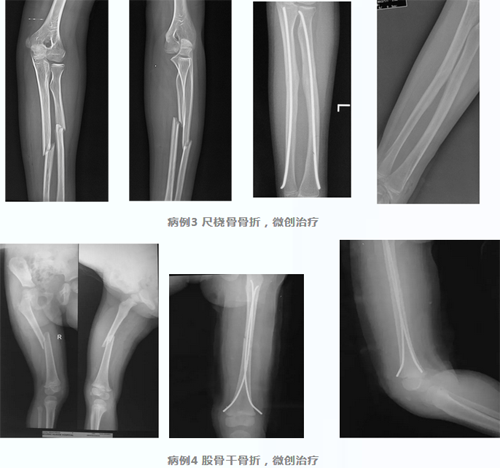

弹性髓内针

儿童长骨骨折传统的治疗方式也是保守治疗,而确实需要手术的患者如果选择切开复位钢板固定的方式,不可避免地增加了手术创伤,同时感染、骨折不愈合、内固定断裂、内固定取出后再骨折的发生率相对高发,因此,专门为儿童开发的弹性髓内针成为治疗儿童长骨骨折的首选。闭合复位经皮置入髓内针,进针点皮肤切口仅1-2cm,不仅微创而且固定牢靠,愈合后取出容易。